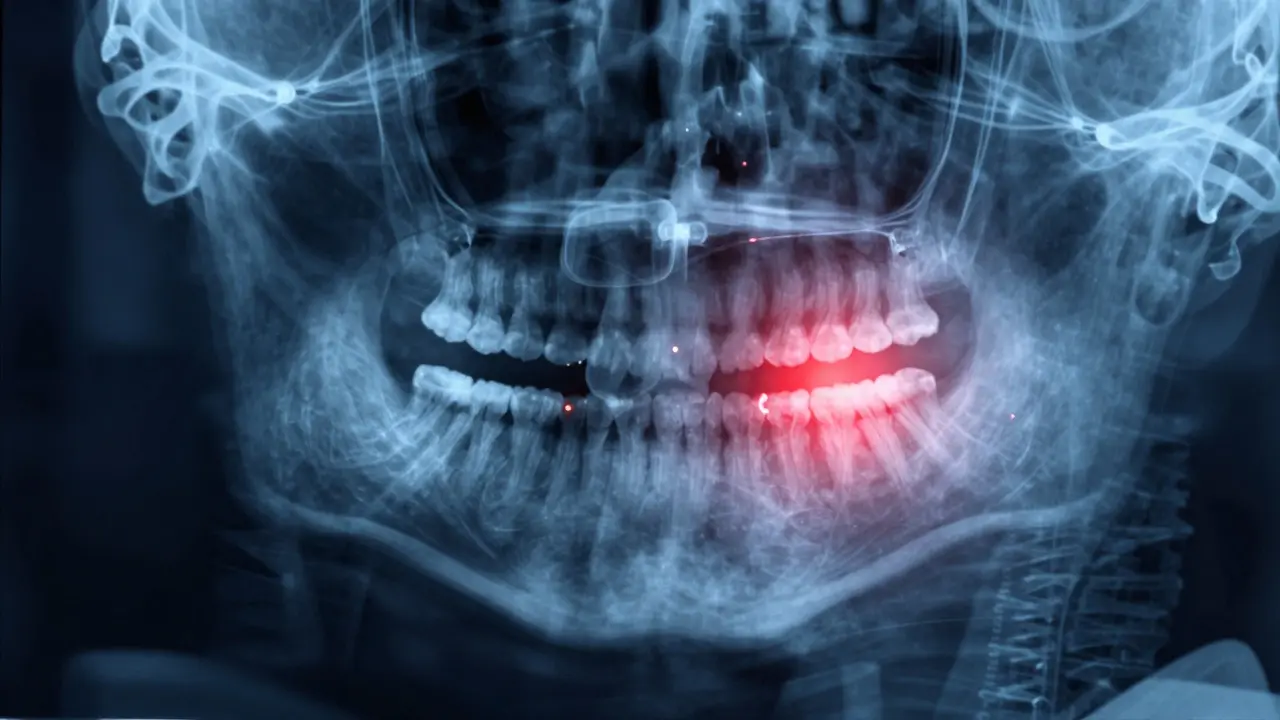

Panoramatický rentgen s označenými impaktovanými zuby moudrosti.

Nemusíte čekat na bolest. Pokud máte 17 až 25 let a nevíte, co se děje za vašimi zuby, dejte si jednoduchý rentgen - panoramatický snímek (OPG). Ten ukáže všechny zuby moudrosti, jejich polohu, směr růstu a vztah k sousedním zubům.